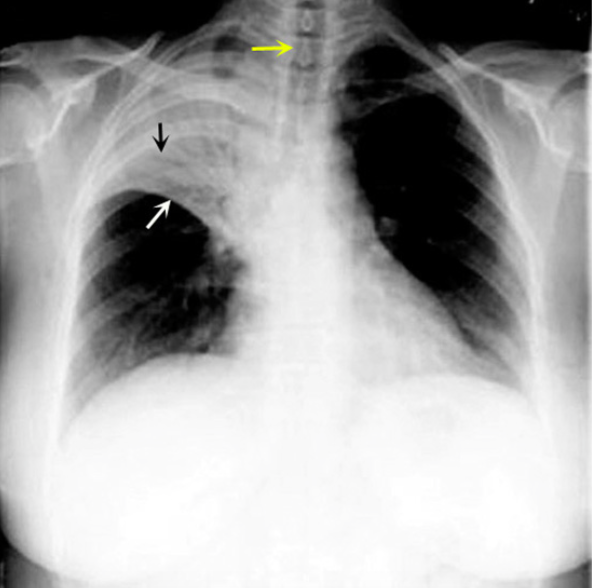

What is this consolidation?

RUL Consolidation